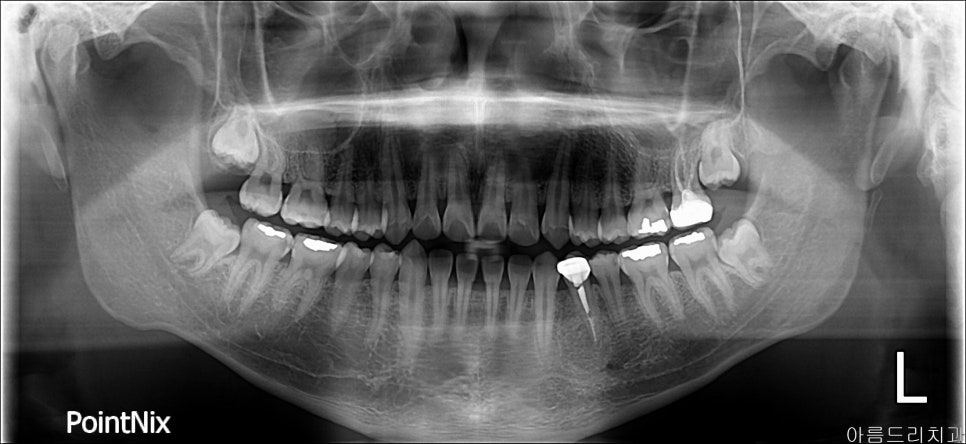

환자분이 최근 들어 왼쪽 아래 사랑니가 지속적으로 붓고 가라앉고를 반복하고 있어 불편하다고 하셨어요. 치과용 구강 전체가 나오는 엑스레이를 찍어보니 사랑니 머리만 올라와 있고 주변 잇몸에 싸여있습니다.

아래 사랑니를 바로 뽑기로 결정하고 사랑니가 아래 신경선 근처에 위치하여 치과용 CT 촬영까지 하셨습니다.